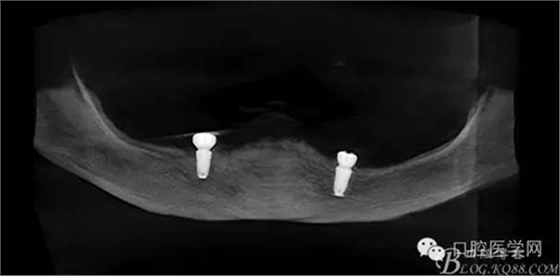

種植覆蓋全口義齒3個月后上球型基臺

種植覆蓋全口義齒下頜牙槽嵴吸收嚴(yán)重,若沒有種植體無法固位。

種植覆蓋全口義齒上頜牙槽嵴條件良好,固位良好。